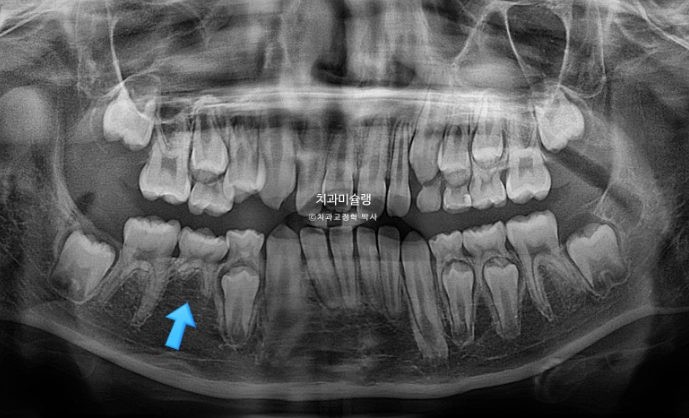

파란화살표 자리에 있어야할 작은어금니가 선천적 결손 상태입니다.

이런 경우 계승영구치가 없어 오래도록 남아있게될 잔존유치를 최대한 보존해서 쓰는 방법으로 치료를 합니다.

잔존유치를 오래 보존해서 사용하기로 했다면 교정 치료 중 불필요한 치아이동에 의해 잔존유치치근이 녹아 짧아지지 않도록 각별히 신경써야 합니다.

유치는 교정력을 받았을때 영구치와 다르게 잘 움직이지 않을 뿐더러, 안그래도 영구치에 비해 뿌리가 약한 상태이니 치근흡수라도 나타나면 발치해야 하는 애매한 상황이 생깁니다.

파란 화살표 잔존유치는 초진에 비하여 치근흡수 없이 잘 보존되었습니다.

다른 영구치들에 치근흡수는 없고 치근평행도는 좋습니다.

선천적 결손이라고 해도 치료를 잘 해주면 별 문제 없이 교정 마무리가 가능합니다.